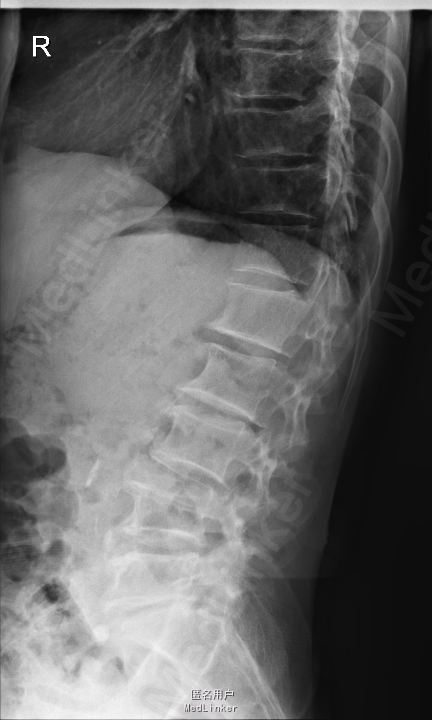

腰痛5年,加重伴左下肢放射性疼痛半个月 患者5年前无明显诱因出现腰痛,不伴下肢放射性疼痛、麻木、无力,腰部活动受限,劳累后加重,平卧休息可缓解。半个月前无明显诱因出现腰痛加重,伴左下肢放射性疼痛、麻木,腰腿活动受限,无低热、盗汗,无纳差、消瘦。

查体:左侧小腿外侧、足背感觉减退,右侧正常,双侧屈髋、伸膝、踝背伸肌肌力5级,左侧踇背伸、跖屈肌肌力4级,右侧踇背伸、跖屈肌肌力4-5级,双侧巴氏征阴性,直腿抬高试验左侧30°阳性,右侧阴性。 辅助检查: X-ray:腰椎退行性变,腰椎节段性性不稳 MR:腰椎间盘突出,腰3/4,4/5,腰4/5节段明显

诊断:腰椎椎管狭窄 处理: 1、完善相关辅助检查,明确诊断,有无手术指证; 2、完善手术评估,有无手术禁忌,手术风险及并发症; 3、在全麻下行腰椎后路减压,腰3/4左侧椎板减压,腰4/5椎间Cage植骨融合内固定术

随访 术后患者下肢麻木感觉较前好转,左侧踝背伸、跖屈肌力4级+,左侧肢体抬高试验阴性。术后MR检查减压彻底 讨论:1、腰椎椎管狭窄手术指证的把握,腰椎后路手术,腰椎椎间融合与椎板减压的选择? 2、术中探查如无明显间盘突出,以椎管骨性狭窄为主,可行腰椎后路椎板减压为主。